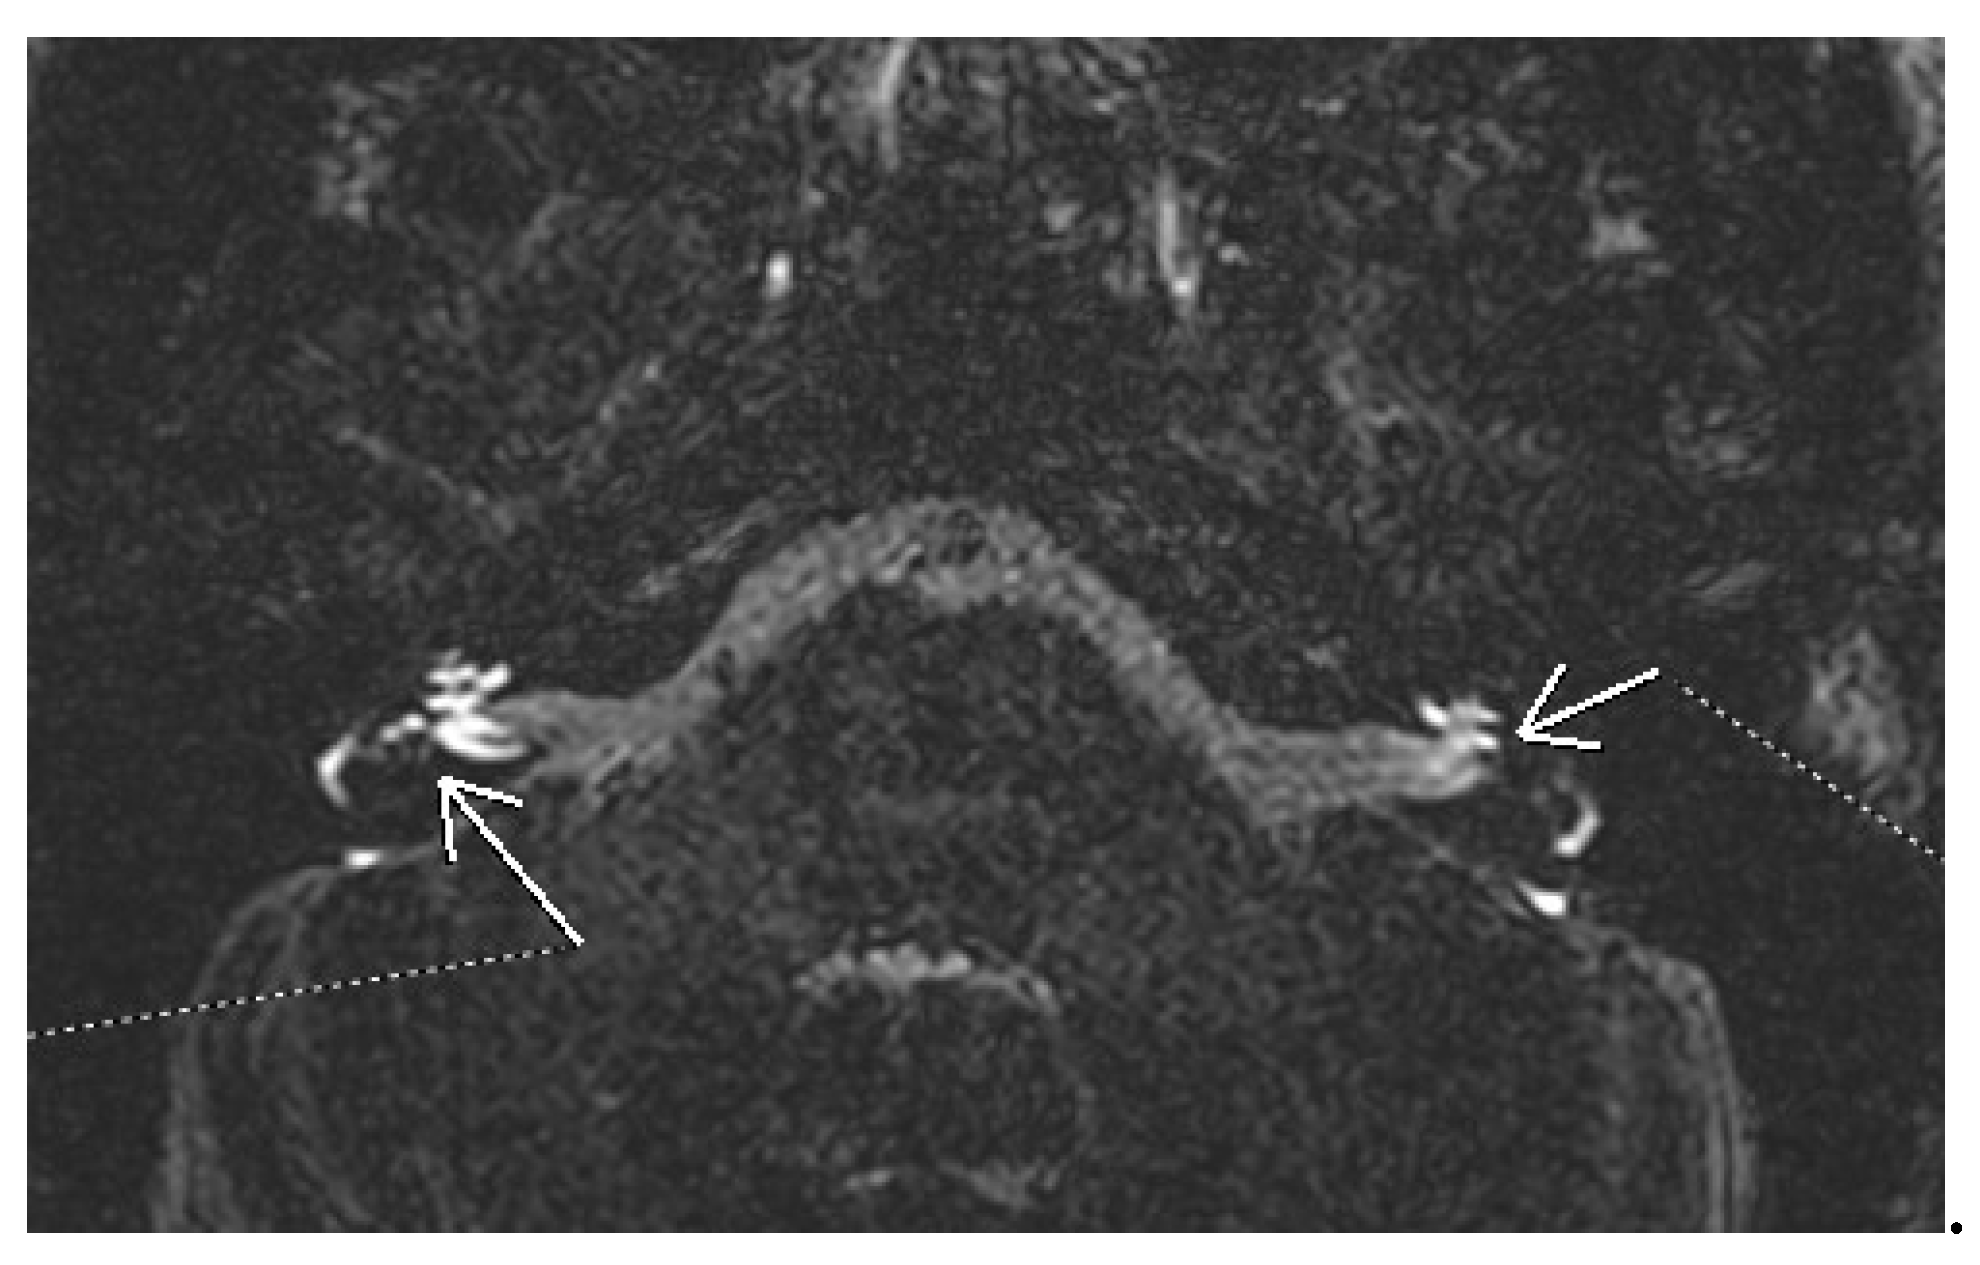

The guideline of the AAO-HNS states in the guideline that physicians may offer as an option magnetic resonance imaging (MRI) of the internal auditory canal (IAC) and posterior fossa in patients with possible Meniere’s disease and audiometrically verified asymmetric hearing loss [35]. Imaging, particularly high-resolution CT and MRI, has a controversial utility [38]. CT may show some modifications compatible with Meniere’s disease. A narrowed vestibular aqueduct is encountered more frequently in affected ears [39,40]. Non-contrast enhanced MRI can show in advanced cases elongation of the saccule, diminished fluid in the cochlear aqueduct, or invisibility of the endolymphatic sac and duct [41,42]. One of the most important steps in the imaging diagnosis of endolymphatic hydrops has been the MRI with gadolinium contrast. Initially, it was administered intratympanically with delayed acquisition. Later it was reported the fact that endolymphatic hydrops can be visualised also after intravenous administration of contrast [43]. The gadolinium based contrast agent accumulates in the perilymphatic space, allowing the visualization of the less permeable endolymphatic space. In 3D FLAIR MRI his space appears as signal voids surrounding hyperintense perilymph, so it highlights changes in the inner ear consistent with endolymphatic hydrops. These changes can be enlargement of the cochlear endolymphatic space, an increment of the vestibular endolymphatic space occupying over one-third of the vestibular space (50% should be significant), and saccule larger than utricle [44,45]. In Figure 1 there is the image of bilateral hydrops seen on a 3D FLAIR sequence evaluated 4 hours after iv administration of gadolinium. Different qualitative and semiquantitative criteria for describing the endolymphatic hydrops have been proposed over the years. The most well-known is the Nakashima criteria. It defines vestibular hydrops as an endolymph/peryplimph ratio of >33%. For the cochlear hydrops, any visual hydrops of the cochlear duct is considered hydropic [46]. Later Barath modified this classification into a 3-point scale categorizing the cochlear and vestibular hydrops into none, grade 1, and grade 2 [47]. Except for hydrops, there are other MRI features compatible with Meniere’s. The non-visualization of saccule has been described in some patients. The proposed explanation is either the collapse or the fistulation noticed in some histopathologic studies [48]. Recently a “round window sign” has been described as a hyperintense signal in the region of the round window on delayed 3D FLAIR. This has been hypothesized as a sign of perilymphatic fistula [49]. Further research is needed to establish the role of MRI in the diagnosis of Meniere disease, to improve and validate the techniques in acquisition and interpretation.

Figure 1. 3D FLAIR MRI of bilateral cochlear and vestibular hydrops.